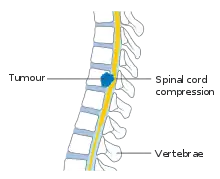

| A tumour causing spinal cord compression | |

Spinal cord compression is a form of myelopathy in which the spinal cord is compressed. Causes can be bone fragments from a vertebral fracture, a tumor, abscess, ruptured intervertebral disc or other lesion.

The most common causes of cord compression are tumors, but abscesses and granulomas (e.g. in tuberculosis) are equally capable of producing the syndrome. Tumors that commonly cause cord compression are lung cancer (non-small cell type), breast cancer, prostate cancer, renal cell carcinoma, thyroid cancer, lymphoma and multiple myeloma.